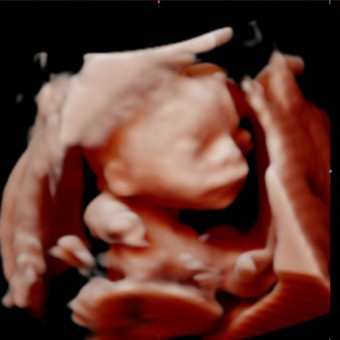

Baby Anastasia

Glorry & Abel Gutierrez

Fountain Valley, CA

May 18, 2026

Hi everyone! Since we do have some stuff from previous children we do ask you check the registry list for things we need for our new baby. We love and appreciate all of you and can’t wait to celebrate together!